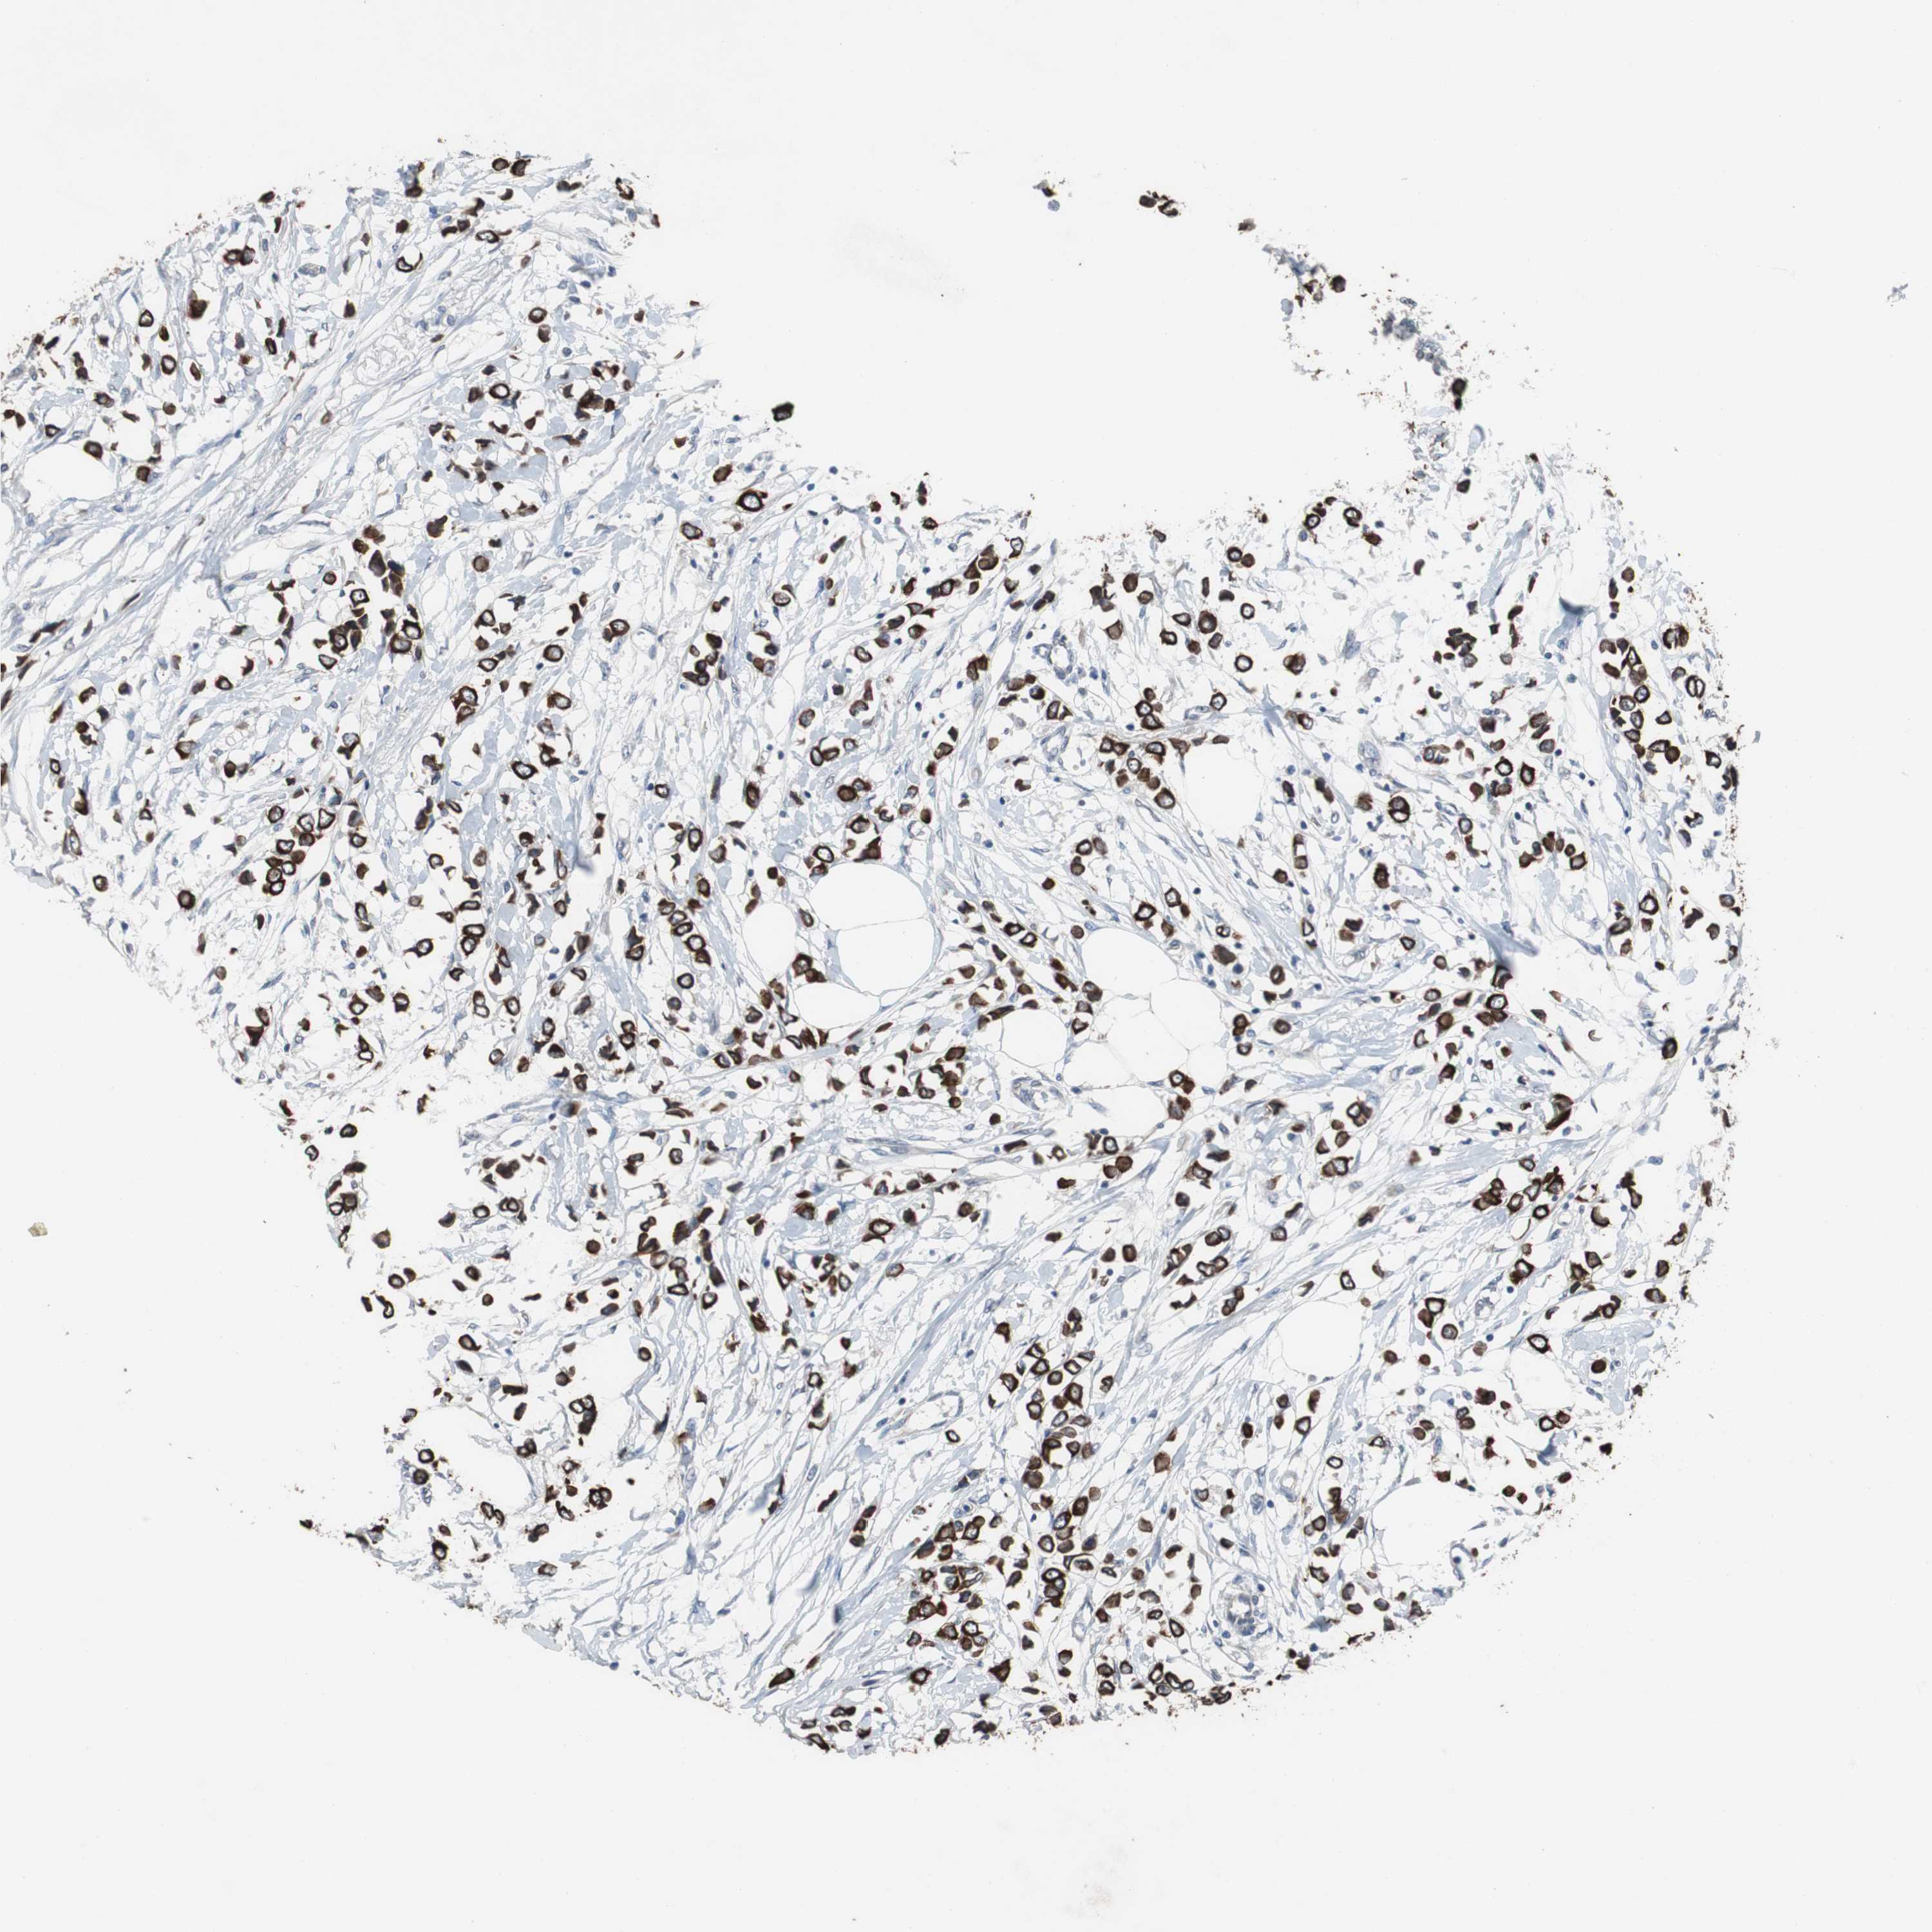

CANCER BREAST CANCER Show tissue menu

BRCA TCGA BRCA VALIDATION PROTEIN EXPRESSION

ANTIBODIES

AND

VALIDATION